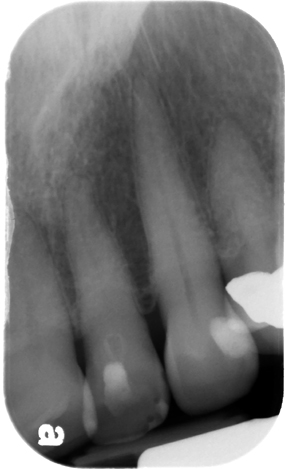

4 / 25

4. (Select ONE OR MORE correct answers)

The radiograph shows evidence of